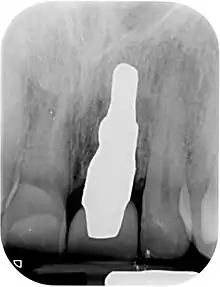

A new attempt was made by Pirker et al 2004 in a human trial with root analogue zirconia implants, but this time by applying differentiated osseoingration on the surface. In 2011 he reported 90% success rate with this method in a 2.5 year human trial.[11]

- Pirker, W; Wiedemann, D; Lidauer, A; Kocher, A (2011). "Immediate, single stage, truly anatomic zirconia implant in lower molar replacement: a case report with 2.5 years follow-up". International Journal of Oral and Maxillofacial Surgery. 40 (2): 212–6. doi:10.1016/j.ijom.2010.08.003. PMID 20833511.